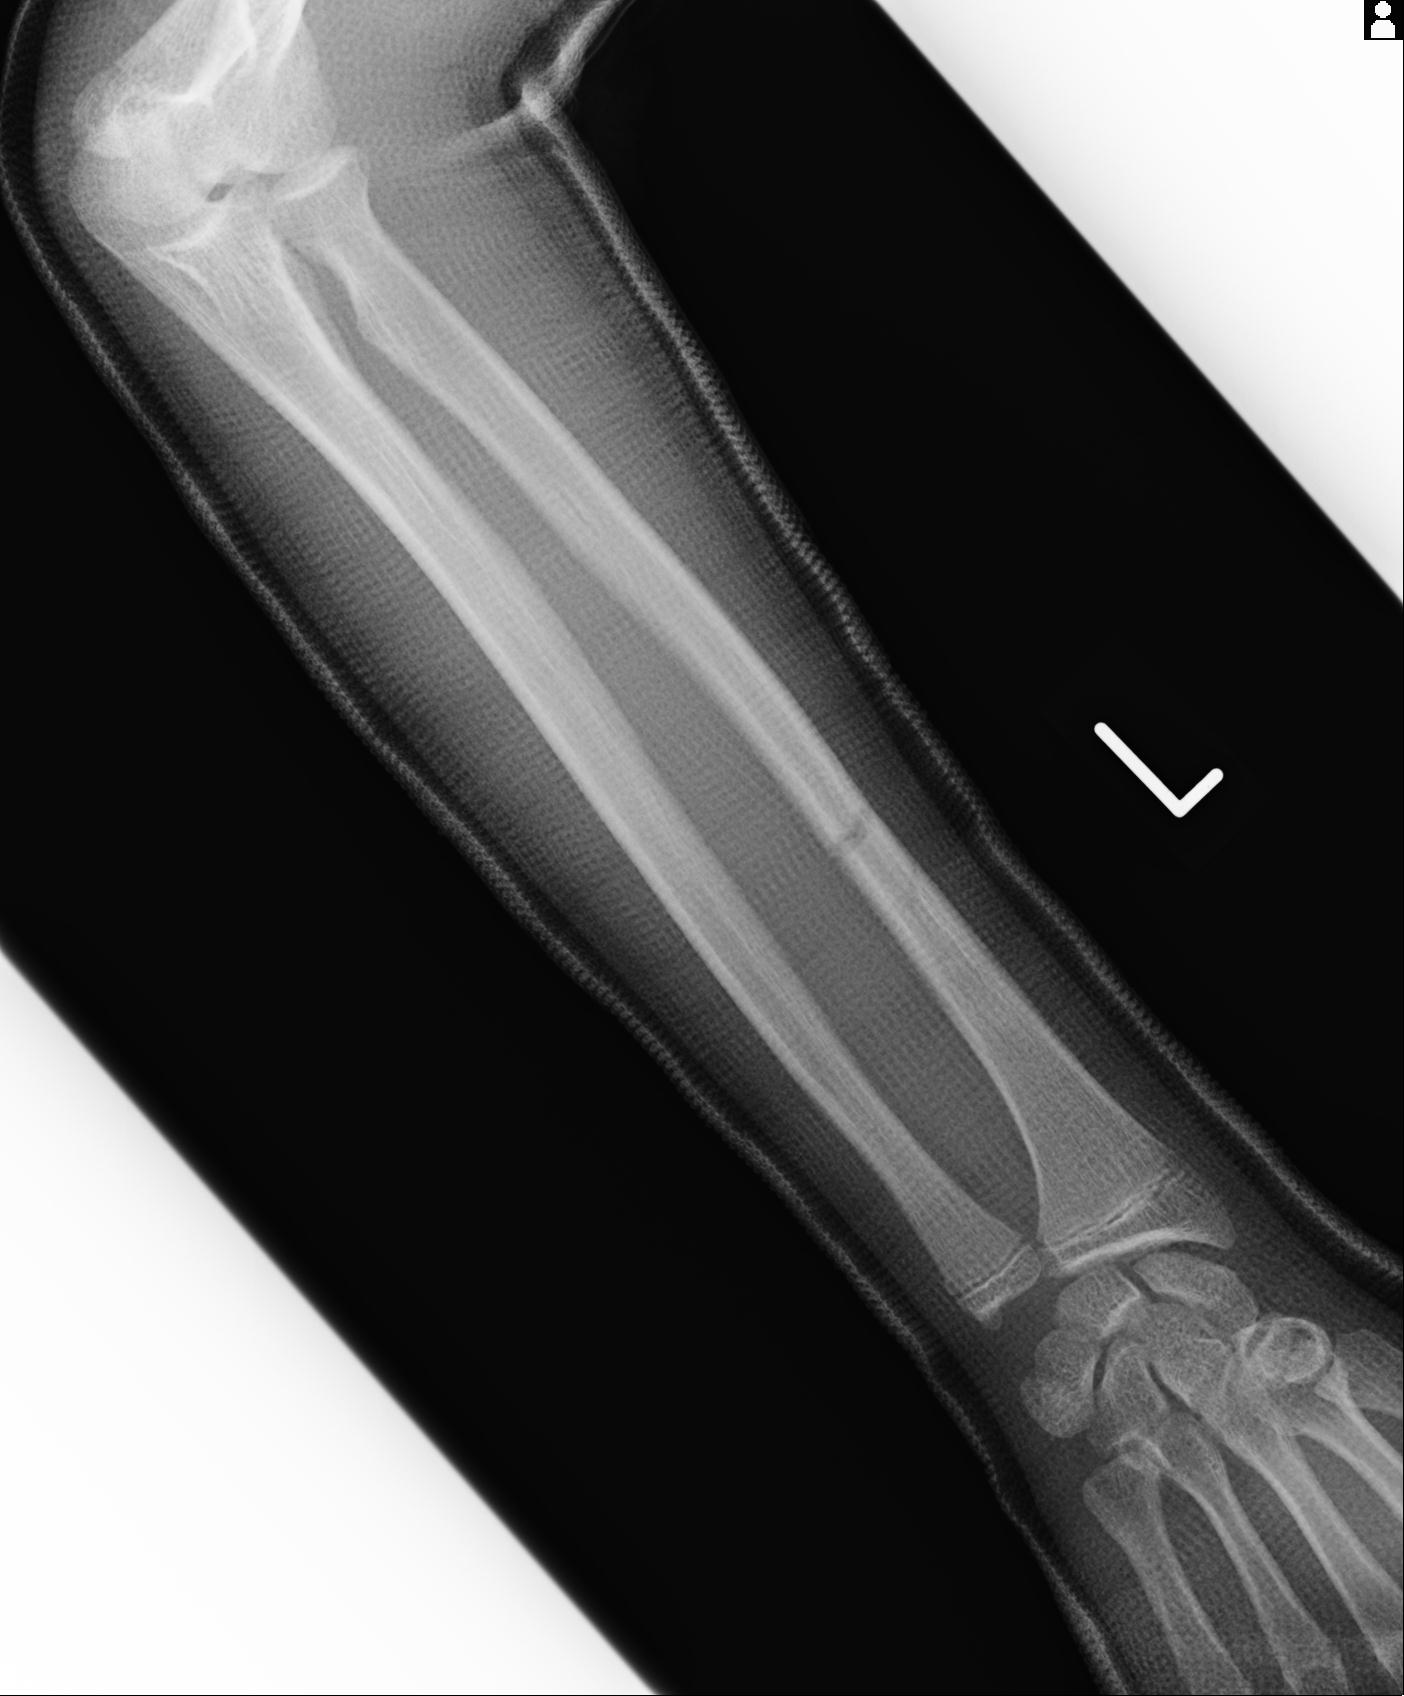

102766 1/5 1/12 左手関節 4R 28歳男性 左橈骨遠位端